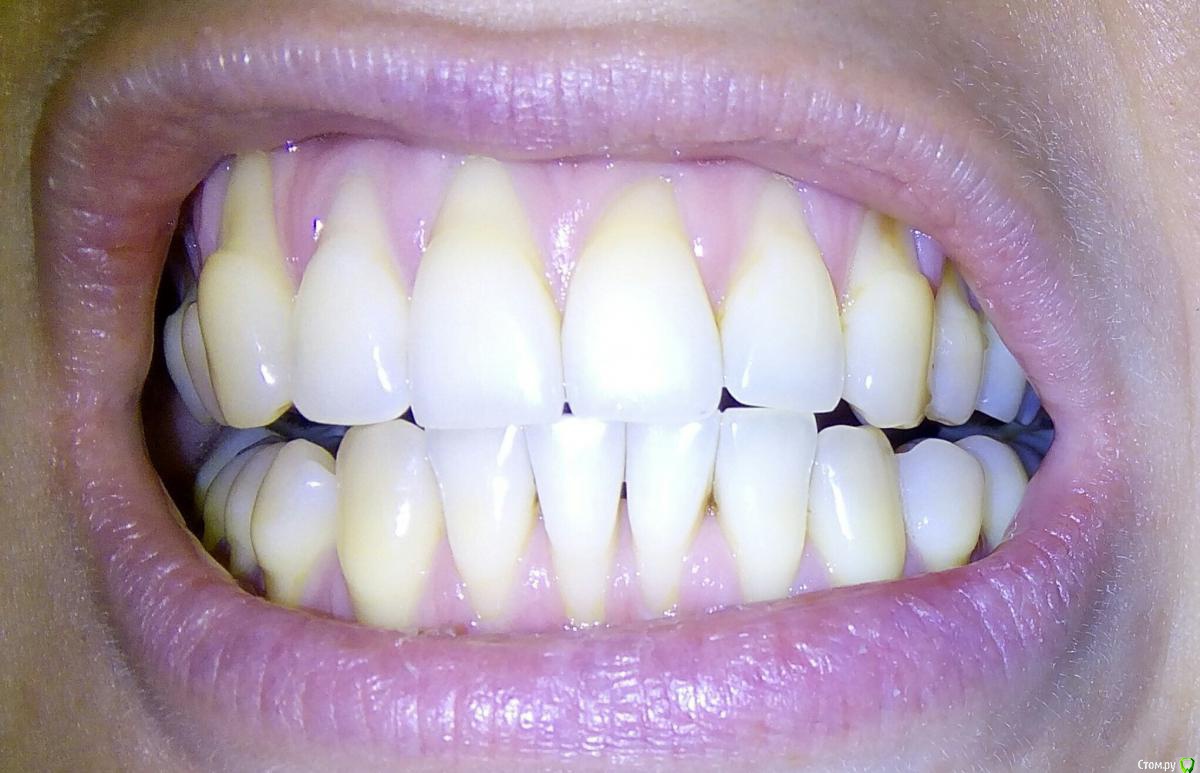

chuvashova_mv Опубликовано 18 июня, 2016 Поделиться Опубликовано 18 июня, 2016 (изменено) Мне 31 год. Тюмень. Сильное оголение корней каждого зуба. Сосочки на месте. Карманов нет. Тонкий биотип десны. Была у неск.ортодонтов, дело не в прикусе.Эндокринолог значит.отклонений не видит (щитовидка в норме, сах.диабета нет, менстр.регулярная сейчас, раньше были сбои), только имт 16,5. Есть ребёнок 3 года, заберем. сама.Гастроэнтеролог - хр.гастродуоденит со школы, желудок работает не в полную меру.Неврология - всд по гипотония.типу., бруксизма нет.Очень сух.кожа с рождения, особенно тяжко зимой.Прилагаются кт и оптг.Вопрос: все очень плохо? У нас в городе вызвались только два врача оперировать, но таких случаев как у меня у них не было.Нужна помощь пародонтологов-хирургов, кто с таким сталкивался. Изменено 18 июня, 2016 пользователем chuvashova_mv Ссылка на комментарий

chuvashova_mv Опубликовано 18 июня, 2016 Автор Поделиться Опубликовано 18 июня, 2016 Если помогут, отправила фото.Чтобы имели представление, насколько сильная рецессия. Радует хотя бы то, что, когда улыбаюсь, не видно. 1 Ссылка на комментарий

AlexanderGudkov Опубликовано 19 июня, 2016 Поделиться Опубликовано 19 июня, 2016 Анамнез и фото - класс!) Причина мне видится в тонком биотипе и агрессивной чистке зубов. По фото все кажется операбельным, возможно потребуется 2 операции 3 Ссылка на комментарий

Ст@ся Опубликовано 19 июня, 2016 Поделиться Опубликовано 19 июня, 2016 На верхней челюсти все операбельно, на нижней результат будет процентов на 70-80 1 Ссылка на комментарий

faity Опубликовано 20 июня, 2016 Поделиться Опубликовано 20 июня, 2016 Судя по ОПТГ дисфункция и деформация ВНЧС, гипертрофия жевательной мускулатуры слева.По фото множественные рецессии и патологическая стираемость зубов.У вас классическая окклюзионная травма которая дала рецессию, стираемость, щелчки в суставе(если уже появились). Вам гнатолог нужен для начала ибо у вас причину сложнее устранить чем последствия в виде стираемости и рецессий.Зубы сжимаете во сне или во время бодроствования? 2 Ссылка на комментарий